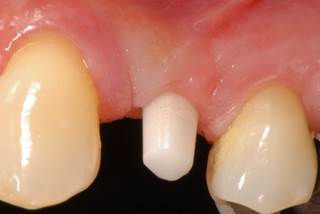

- Pacientes que buscan un resultado especialmente estético en la región anterior

- La encía alrededor de las restauraciones sobre estos implantes siempre tiene un aspecto absolutamente saludable sin signos de inflamación